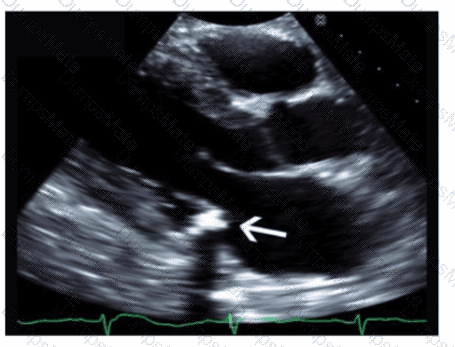

Which structure is indicated by the arrow on this image of a normal valve?

AE-Adult-Echocardiography Question 7

Options:

A.

Posterior leaflet

B.

Septal leaflet

C.

Non-coronary cusp

D.

Left coronary cusp